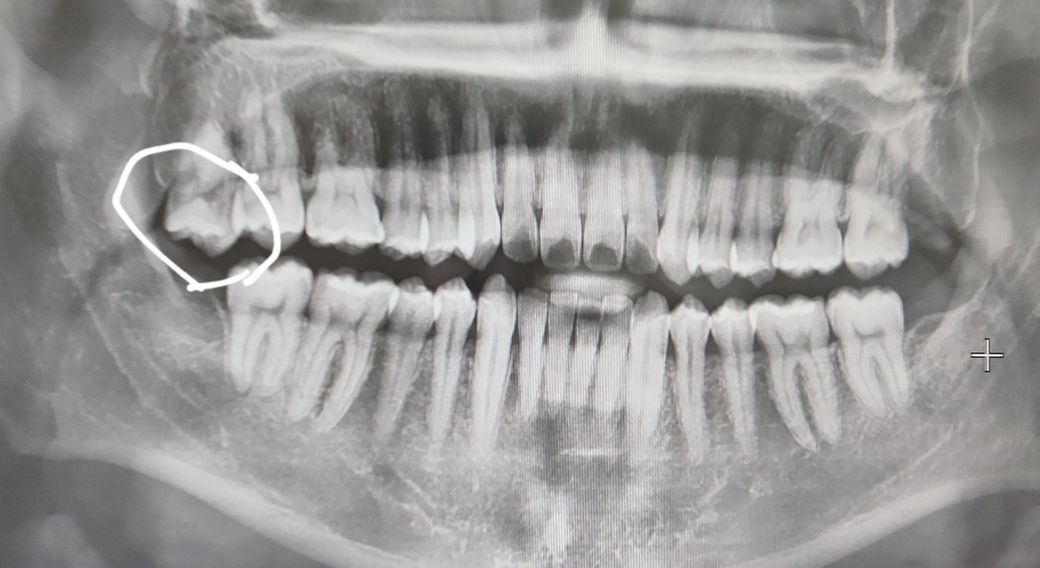

사랑니 이 정도면 언제쯤 뽑아야 할까여?

사랑니 많이 내려온다고 뽑아라고 듣긴 했는데 이정도면 언제쯤 뽑는게 좋을까여? 마주보는 치아도 다 뽑아서 지금 이제 1개 남았습니다.

사랑니는 이미 충분히 나온 것으로 판단되며 지금 바로 발치를 하셔도 괜찮을 것으로 보입니다.

사랑니에 대합되는 치아가 없어서 많이 정출된 상태이니 발치를 하시는게 좋을것같습니다.

사랑니를 방치하는 경우 앞의 치아에 영향을 주거나 잇몸에 염증을 유발할 가능성이 높기에 문의주신 사진의 사랑니는 빠른시일내에 발치하길 권합니다.

기능을 하지 않는 사랑니 이고 정출이 되어 있다면 다른 조직에 문제를 발생시킬수 있기 때문에 예방차원에서 발치를 해주는것이 좋을수 있습니다.

언제뽑아도 상관없으나 어차피 지금 맞닿는 치아가 없으므로 계속 내려올것입니다(정출현상) 그렇게되면 볼을 자주 씹을 수 있고, 사랑니 및 그 옆 어금니에 충치도 생길 수 있습니다